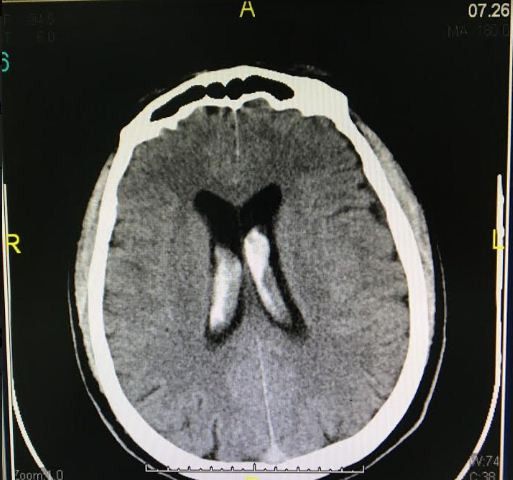

Kết quả chụp CT scan cho thấy ông H. bị: xuất huyết màng não, xuất huyết trong các não thất, xuất huyết trong các bể dịch não - tủy ở nền sọ, viêm đa xoang. Bệnh nhân nhanh chóng được chuyển sang khoa Ngoại thần kinh để được can thiệp giúp ngưng chảy máu vì nghi ngờ có vỡ túi phình dị dạng mạch máu não.

| Hình ảnh xuất huyết não thất |